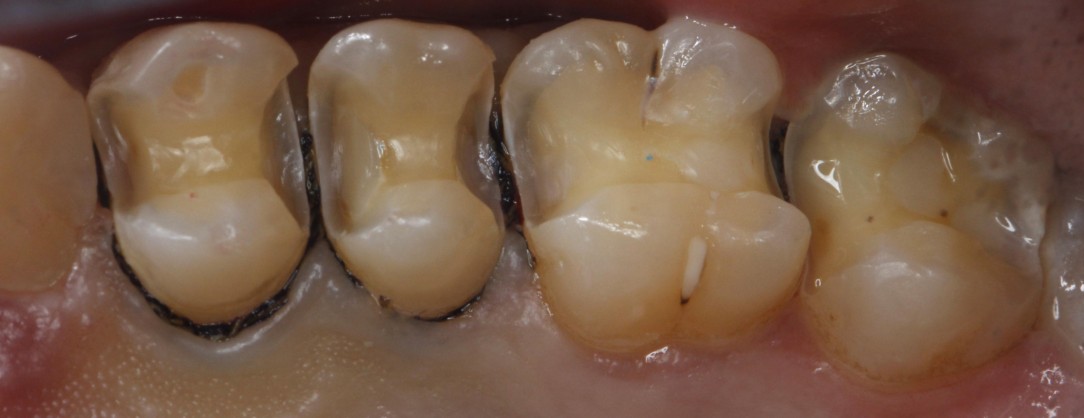

门诊经常遇到常年把碳酸饮料当水喝的患者,严重损伤了牙齿的健康,检查发现牙齿脱矿.龋坏特别严重,特别是邻面龋坏,治疗也非常麻烦,很多情况下,简单的补牙都解决不了长久性问题,想要经久耐用,可以选择嵌体,高嵌体,全瓷牙冠修复,更重要是杜绝不良嗜好;有图有真相!我们采用德国西诺德瓷睿刻即刻修复系统,等待1小时,完成当日修复。